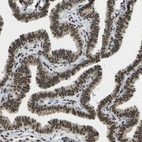

Immunohistochemical staining of human fallopian tube shows strong nuclear positivity in glandular cells.